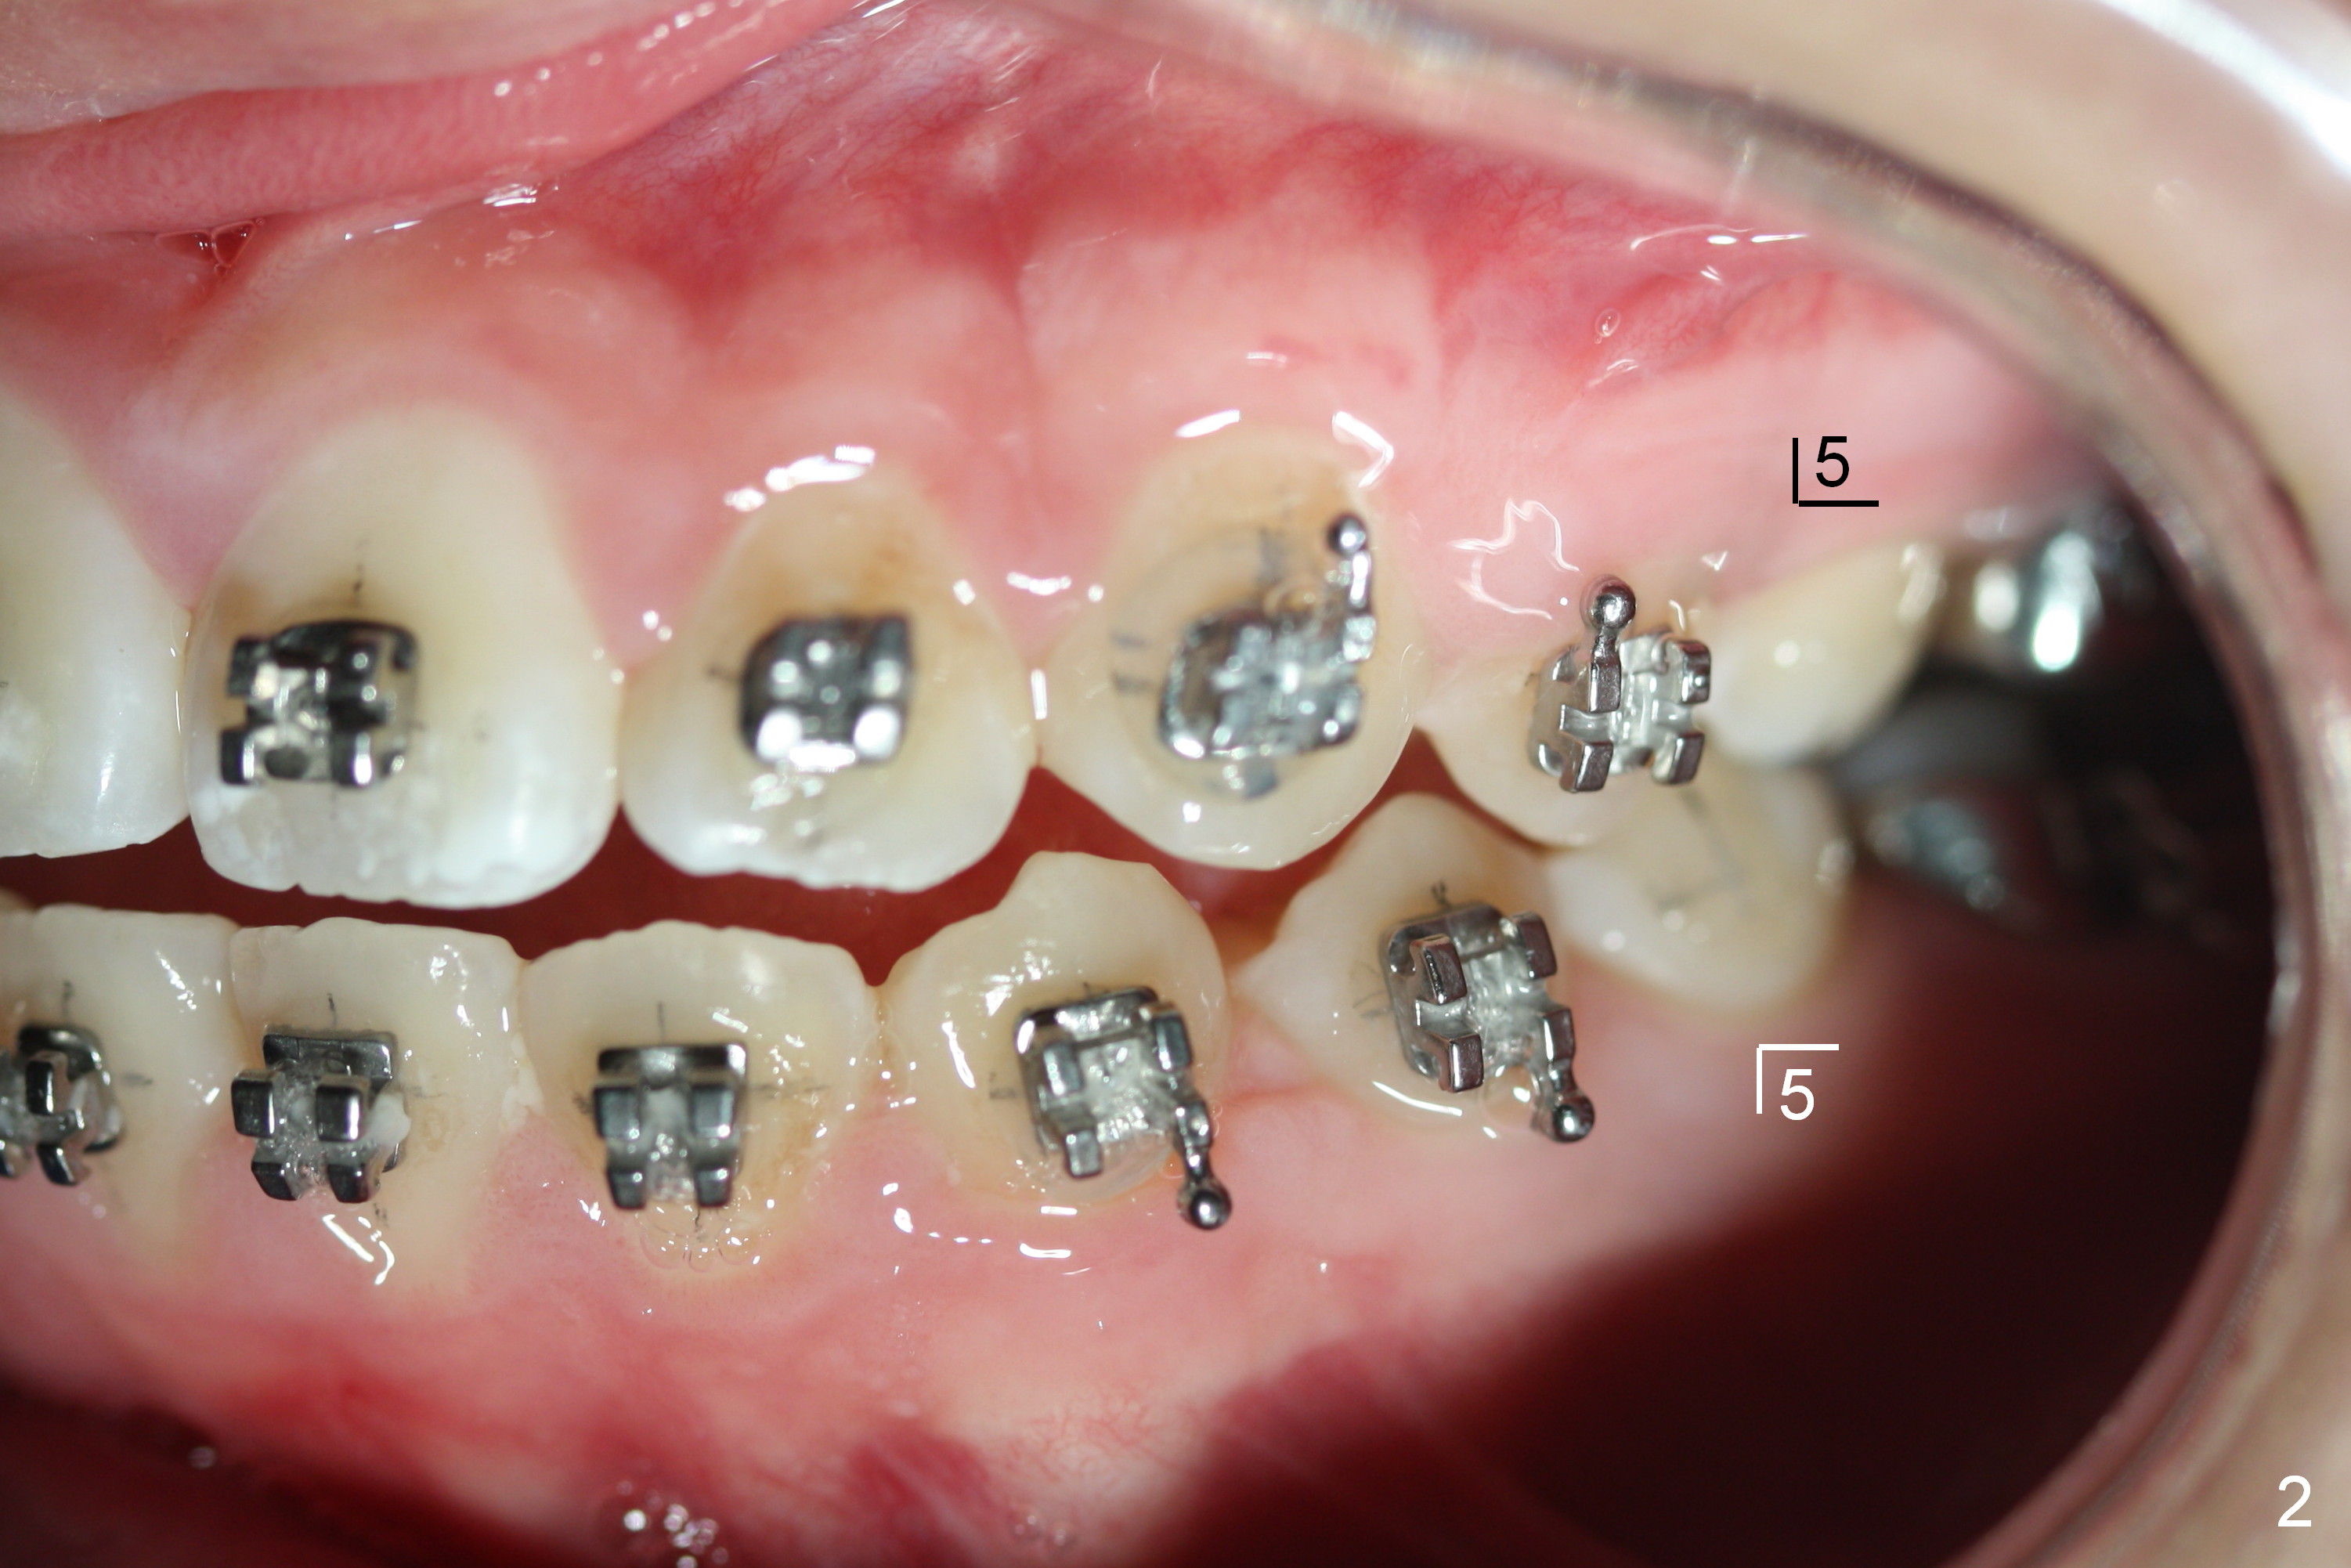

A 15-year-old Spanish female has been in orthodontic treatment for 2 years 3 months (1 2 3). Facial profile is convex (same as preop (Fig.5-8)) with anterior open bite (Fig.1,2). Four bicuspid extraction is considered. Since brackets of the 2nd bicuspids have been lost (Fig.1,2) and there are pathologies associated with the lower ones (Fig.3,4), all of the 2nd bicuspids have been extracted. Plan is to retract the 1st bicuspids, canines and incisors sequentially. How to close the anterior open bite?